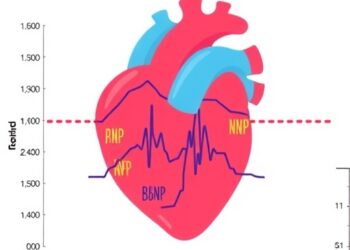

LAD/BSA, NT-proBNP Predict Pediatric Heart Death

Pediatric left ventricular non-compaction (LVNC) has long posed a significant challenge for cardiologists and pediatric specialists due to its unpredictable...